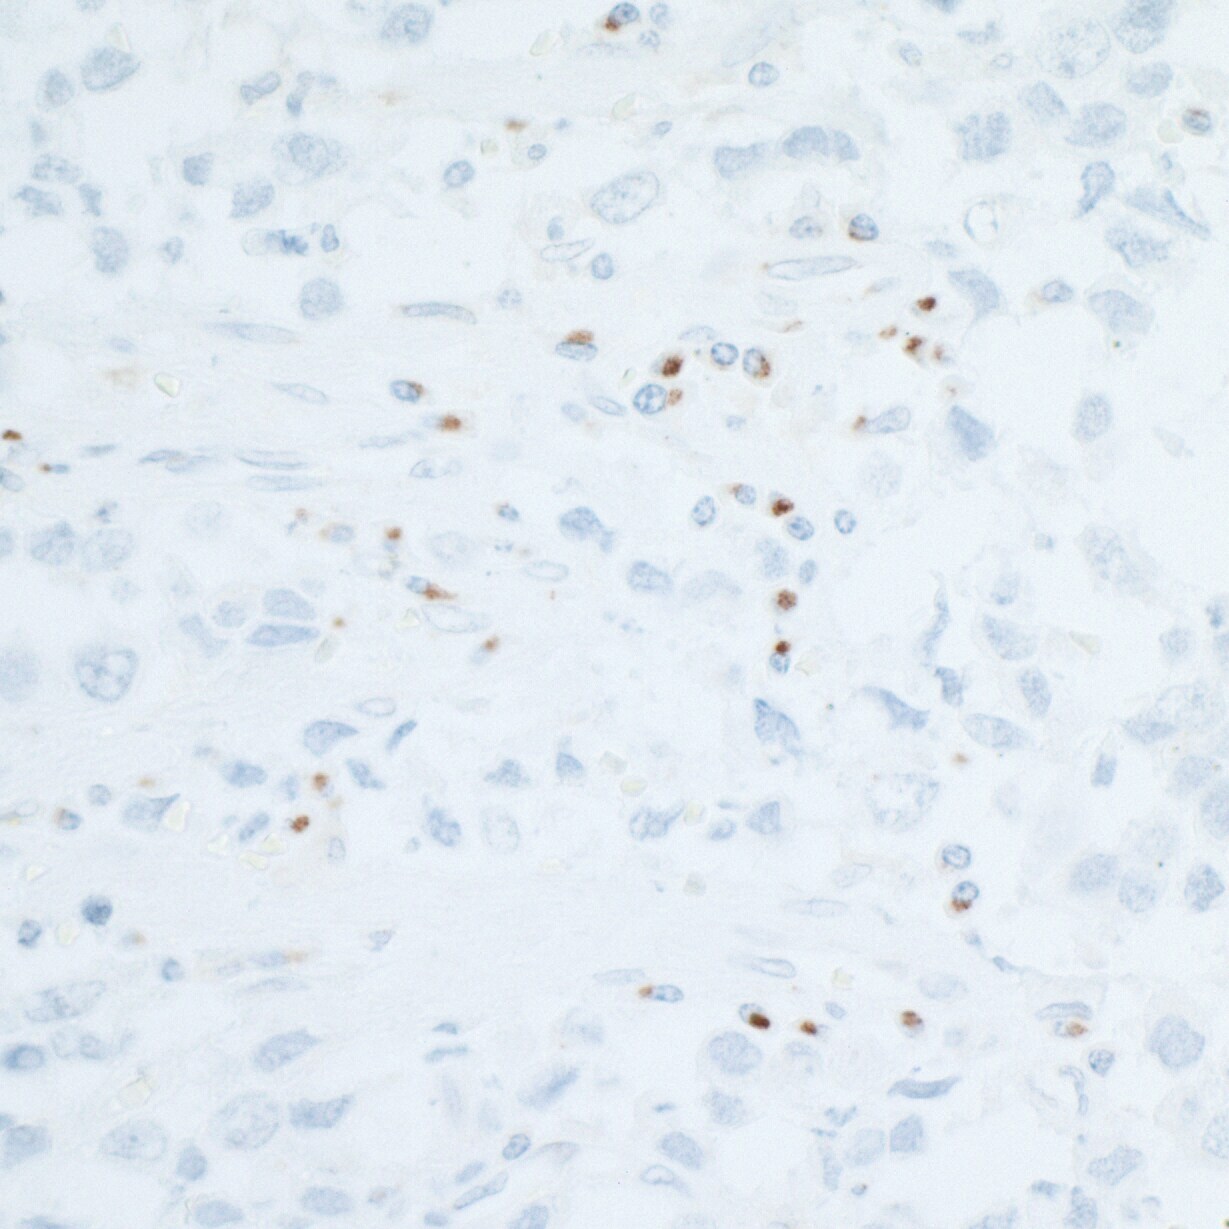

- Submitted by

- Invitrogen Antibodies (provider)

- Main image

- Experimental details

- Detection of human CD86 in FFPE seminoma by IHC.Antibody: Rabbit anti-CD86 recombinant monoclonal [BLR030F] (A700-030).Secondary: HRP-conjugated goat anti-rabbit IgG (A120-501P). Substrate: DAB.